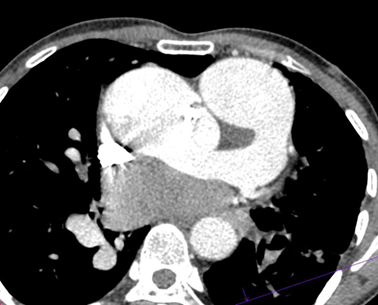

Persistent truncus arteriosus is an uncommon complex congenital heart disease. Without surgical intervention, the prognosis is not good. Very few untreated cases of truncus arteriosus survive to maturity. We report an exceptional case of uncorrected truncus arteriosus surviving into adulthood of type a3 variant -van praagh classification as a 26-year-old male who had well tolerated dyspnea since birth. Our patient showed a single(right) pulmonary artery arising from the common arterial trunk supplying the right lung and absent main and left pulmonary artery with collateral supply to the left lung consistent with the truncus arteriosus type a3-van praagh classification